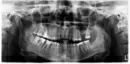

Уже второй месяц у меня болит нижняя челюсть слева. Когда пью холодную воду, болит вся челюсть. Когда кусаю что-то твердое - появляется резкая боль в 7-ом или 6-ом зубе, точно не понятно, какой зуб болит, потому что боль всегда отдает в челюсть. На рентгене ничего не видно, стоматолог не может понять, в чем дело. Также на рентгене под 6-ым и 7-ым зубами какое-то темное пятно.

По данному рентгеновскому снимку - ортопантомограмме, можно сказать что в области верхушек медиального и дистального корней 4.6 зуба (6-й зуб снизу справа) есть очаги воспаления - хронический апикальный периодонтит, что может провоцировать боль при накусывании. Корневые каналы зуба следует перелечить (механически и медикаментозно обработать, поставить лекарство на основе гидроокиси кальция до полного снятия воспаления, а после постоянно запломбировать).

Для лечения необходимо обратиться к стоматологу терапевту. Зубы 3.6 и 3.7 (слева внизу 6 и 7) надо сделать прицельный рентгеновский снимок. Скорее всего, есть апроксимальный кариес с медиальной стороны на зубе 3.6. Зуб, возможно, придется депульпировать (удалять нерв). Необходим осмотр, чтобы более подробно ответить на ваш вопрос. Проконсультируйтесь очно с другим специалистом.